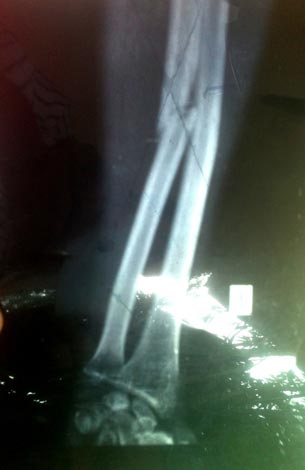

![]() |

| Ảnh chụp xương tay ông Thành bị gãy. |

| Kết luận điều tra bổ sung số 09/QĐ của cơ quan CSĐT Công an huyện Phú Lộc ngày 3/10/2014 cho biết: Xác định rõ bị can Lê cầu là người đã dung thanh gỗ tràm đánh gãy tay trái của ông Phan Gia Thành gây thương tích tổn hại sức khỏe 4% và xác định ông Lê Văn Quý không tham gia đánh nhau với ông Thành và ông Cầu nên cơ quan điều tra không có căn cứ để xử lý. Tại kết quả pháp y số 10 - TL /GĐPY ngày 17/9/2014 của Trung tâm Pháp y tỉnh Thừa Thiên - Huế đã xác định rõ: Ông Phan Gia Thành bị vết gãy xương trụ cẳng tay trái là đường gãy chéo hướng tác động theo trục cẳng tay từ trên xuống dưới… Từ những tài liệu chứng cứ được thu thập, cơ quan CSĐT Công an huyện Phú Lộc có đủ căn cứ xác định Lê Cầu phạm tội "Cố ý gây thương tích" quy định tại điều 104 BLHS. |